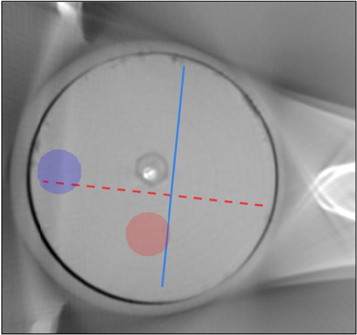

The image quality of the reconstructed virtual monoenergy images (VMIs) was evaluated by assessing the standard deviation (SD) from a circular region (diameter = 50 pix) susceptible for beam hardening artefact (figure 3, blue annotation), and by assessing the uniformity as standard deviation from the uniform circular region (diameter = 50 pix) from each sample (figure 3, red annotation). In addition, the horizontal and vertical HU profiles were evaluated from a single sample (figure 3).

Figure 3. Profile annotation for the cupping evaluation. Red annotation is the vertical profile and blue annotation is the horizontal annotation.